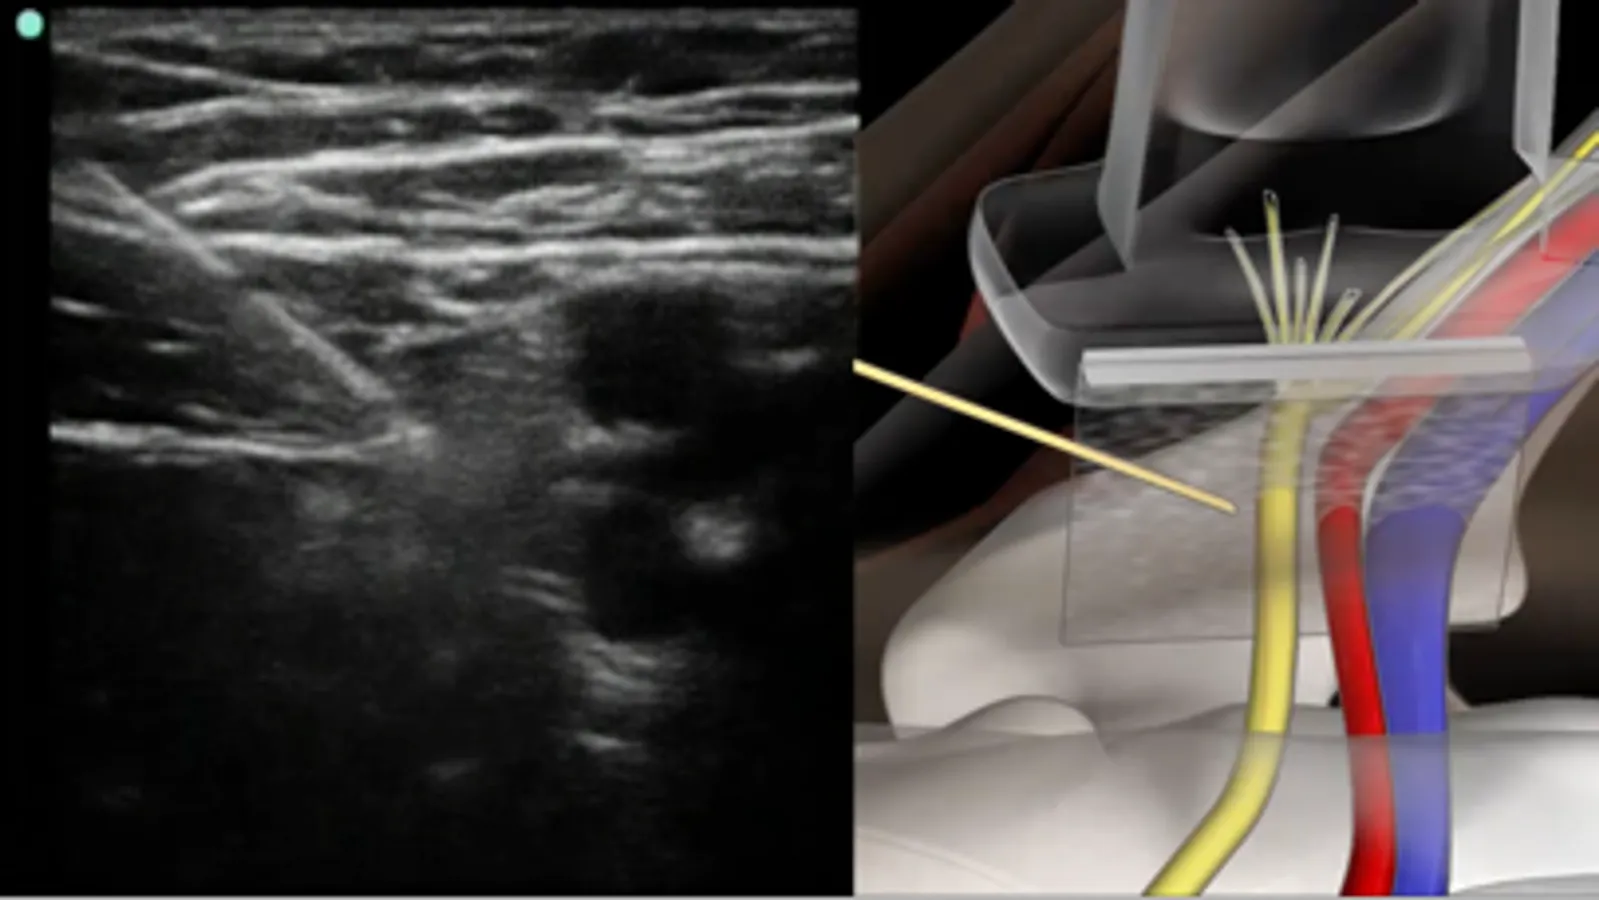

A unique system that combines live sonoanatomy via ultrasound scans, 3D animated anatomy and real time video of the performance of regional anaesthetic nerve blocks. All elements are combined and synchronised with audible narration.

* 3D Animated anatomical models, interlinked with live ultrasound scans.

* Synchronised (US and camera) nerve mapping scans.

A tab system gives the user access to anatomy, procedure, tips and equipment. The anatomy tab gives an overview of anatomy related to the specific block, it includes schematic diagram’s which can be expanded to full screen. The procedures tab is a full pictorial and text guide to the performance of the specific block, including annotated ultrasound screen captures to help visualise nerves. The tips tab contains useful advice related to the selected block, also included is advice on the use of ultrasound and local anaesthetics.

Serratus anterior